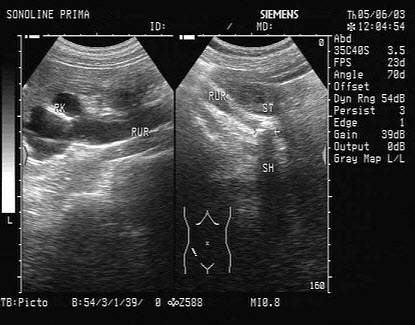

27、单项选择题

男性,右侧阴囊空虚,左侧可触及,于腹腔见一个椭圆形低回声光团,边界清晰,回声尚均匀,CDFI:血流信号丰富。如图所示,考虑为()

A.隐睾并精原细胞瘤

B.腹腔囊肿

C.腹腔淋巴结

D.畸胎瘤

E.腹腔淋巴瘤